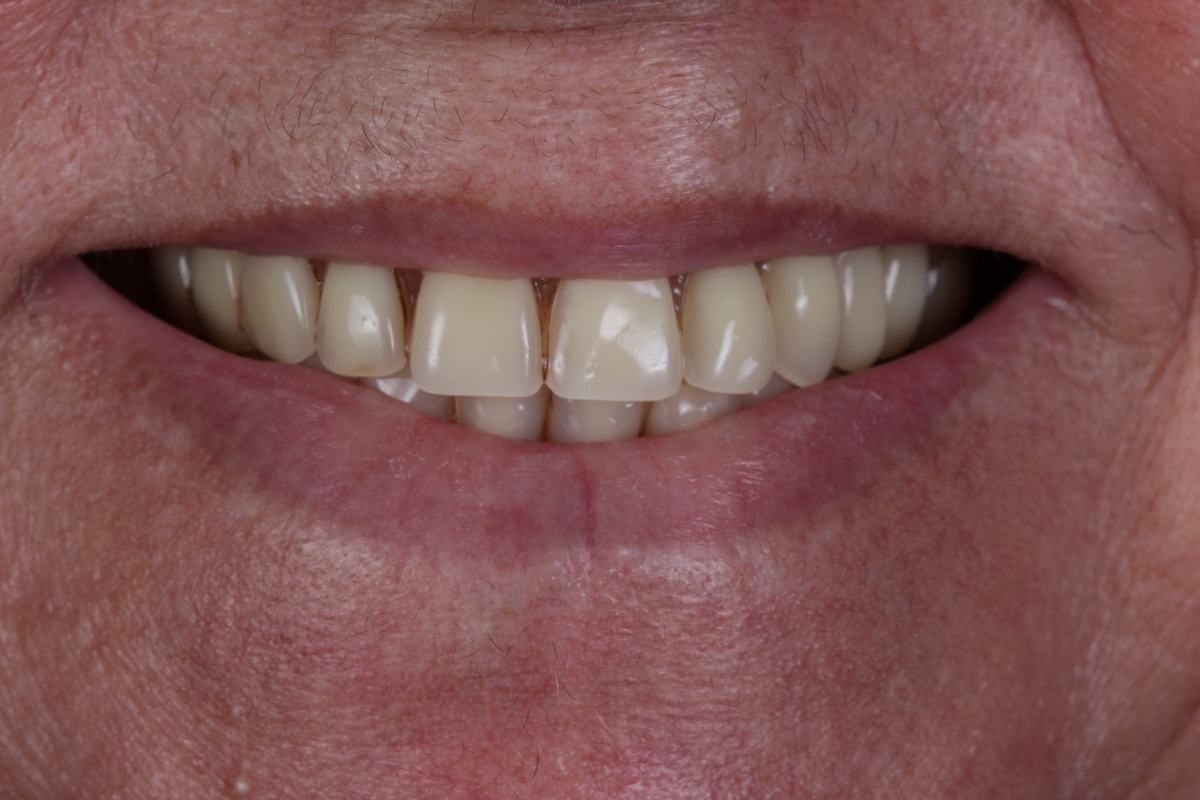

PRÓTESE TOTAL FIXA EM IMPLANTES

E.M.S.